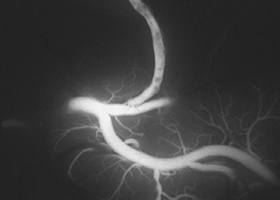

38歳、もやもや病、左半身一過性脳虚血発作

[画像所見]

頭部MRA(脳血管の脱落、赤丸部) 左

術前MRA -

術後MRA

術後はバイパス血管が脳内に向かって出現しています(赤丸印)。